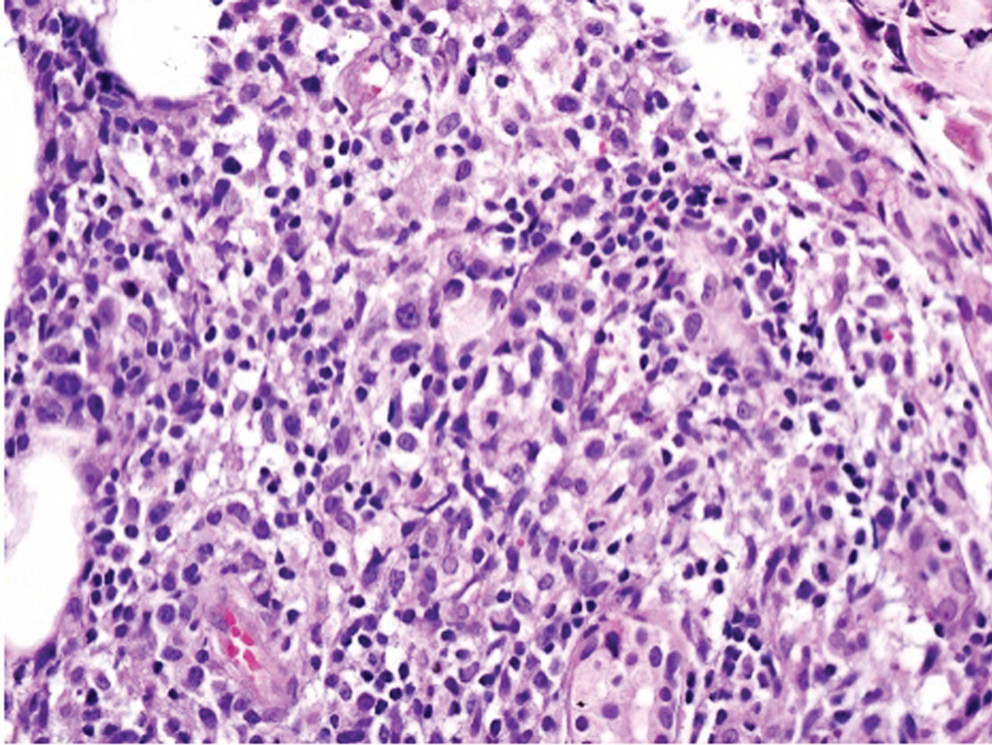

Учитывая отсутствие в биоптате признаков васкулита, гистологический материал пациента был направлен на пересмотр в НИИ онкологии им. Н.Н. Петрова, где было выполнено иммуногистохимическое исследование с антителами ALK, DSF3, CD3, CD4, CD8, CD20, CD30, CD56, Ki-67. По результатам исследования в дерме определялись плотные крупноочаговые инфильтраты, расположенные преимущественно в средних и глубоких отделах дермы и проникающие в дольки подкожной жировой клетчатки (рис. 3). Инфильтраты состояли из крупных лимфоидных клеток с иммунобласто- и центробластоподобной морфологией (рис. 4) и малых лимфоцитов. Крупные лимфоидные клетки экспрессировали CD3+, CD4+ и CD30+, были негативны к ALK (рис. 5–7). Ki-67 (индекс пролиферативной активности) был положителен преимущественно в крупных лимфоидных клетках и составлял примерно 30% всех клеток инфильтрата (рис. 8). Гистологические изменения и иммунофенотип опухолевых клеток соответствовали ЛиП типу С.

Рис. 4. Микрофотография, ×100, гематоксилин-эозин. Дермальные инфильтраты, представленные крупными лимфоидными клетками с иммунобласто- и центробластоподобной морфологией и малыми лимфоцитами

Fig. 4. Microphotography, ×100, hematoxylin-eosin. Dermal infiltrates consisted of large lymphoid cells with immunoblast- and centroblast-like morphology and small lymphocytes